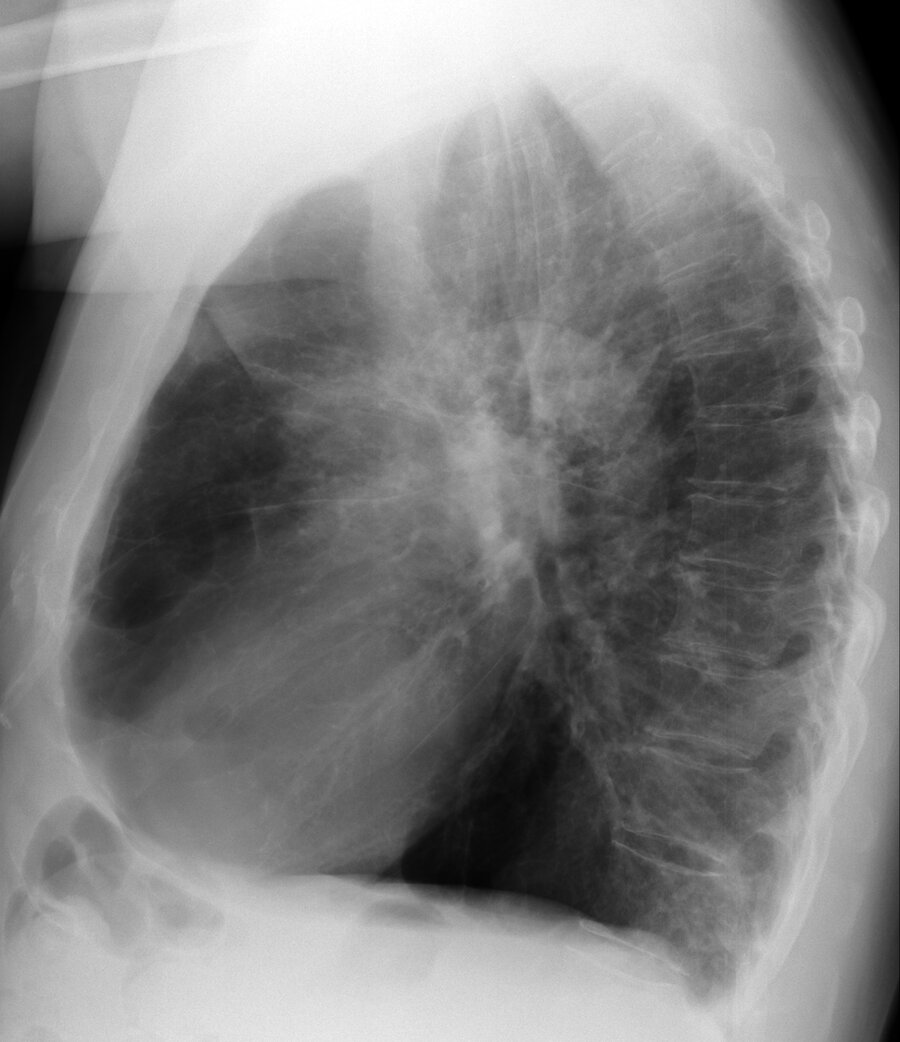

A 72-year-old patient is evaluated for worsening dyspnea on exertion. They have a longtime history of cigarette smoking.

Chest radiograph is shown.

Which of the following is the most likely abnormality seen on this frontal chest radiograph?

Hilar adenopathy

Interstitial lung disease

Mediastinal mass

Prominence of the pulmonary arteries

A 69-year-old man is evaluated for chronic dyspnea without cough. Pulmonary function demonstrates an obstructive defect that persists following bronchodilator administration.

Chest radiographs are shown.

Which of the following conditions is the most likely radiographic diagnosis?

Bronchiectasis

Bullous lung disease

Left lower lobe pneumonia

.Hodgkin lymphoma